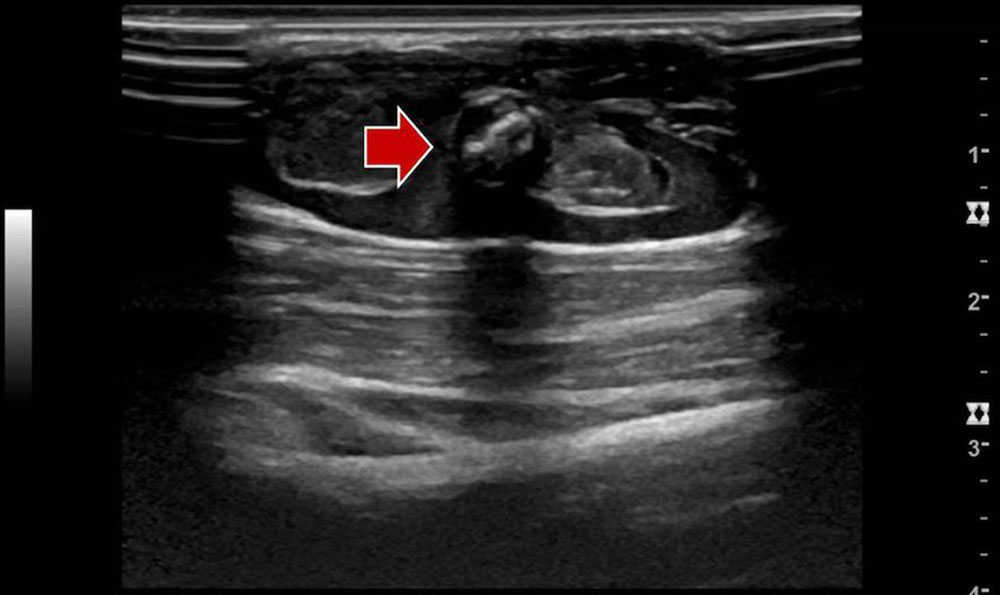

• Lymphatic malformation: In B-mode ultrasound, macrocystic lymphatic malformations appear as echo-free cysts with a thin wall and possibly septa. Blood vessels in the septa and cyst walls are occasionally identifiable. In contrast to venous malformations, macrocystic lymphatic malformations are not as compressible and rather elastic. Microcystic lymphatic malformations show a very heterogeneous ultrasound pattern. In addition to small echo-free microcysts, hypoechoic and hyperechoic masses can also be detected. The cysts themselves do not enhance contrast medium in CEUS. There is no flow on CCDS.